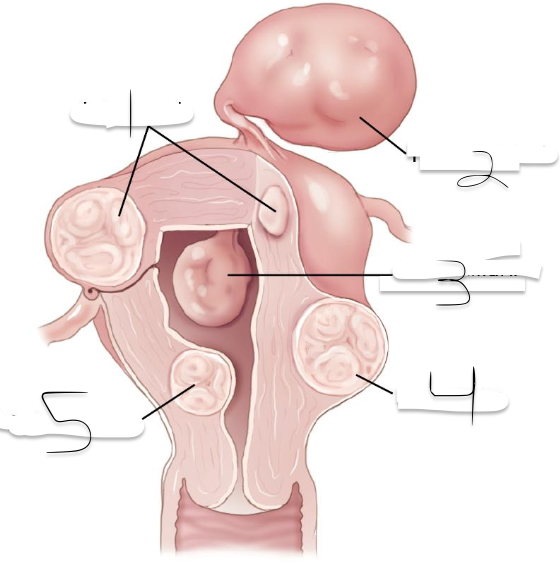

Leiomyomas can be_______________________?

Submucosal, Intramural, Subserosal

(displacing or distorting endometrial cavity with subsequent irregular or heavy menstrual bleeding, Infertility)

What kind of Leioyomas can this be?

Submocosal

(confined to myometrium; most common type): may enlarge to cause pressure on adjacent organs; Infertility or recurrent pregnancy loss.

What kind of Leioyomas can this be?

Intramural

(projecting from the peritoneal surface of uterus): Can become pedunculated and appear as extrauterine masses, may enlarge to cause pressure on adjacent organs

What kind of Leioyomas can this be?

Subserosal

1?

Intramural

2?

Pedunculated

3?

Intracavitary

4?

Suberous

5?

Submuscosal